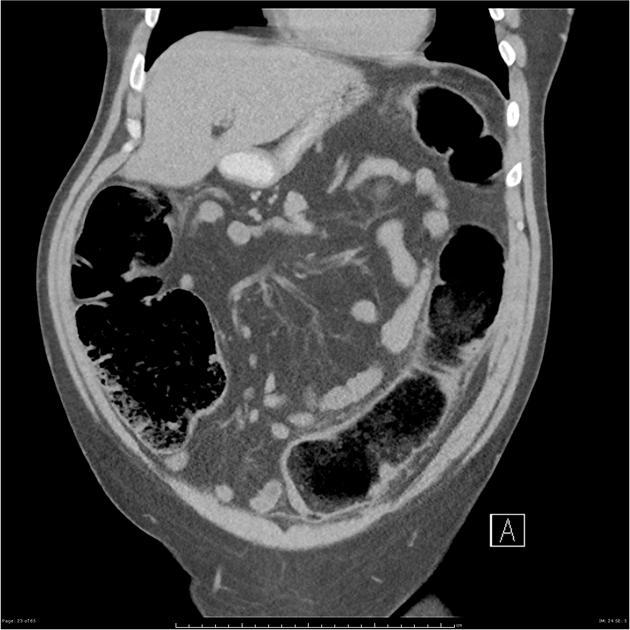

Image radiologique TDM de l'occlusion

colique est :

- La distention colique segmentaire ou diffuse

du colon avec diametre depasse de 6cm et

sa paroi est bien epaisse . En cas de valvule

Bauhin est incontinent la distention peut s'etendre

au anse ileon jusqu'au jejunum . |

- L'image de la lesion et aspect de la

cite de l'obtacle . Le colon amont de l'obtacle est

tres dilate et le segment du colon en aval etre

normale ou collabe |

Image de l'occlusion du colon

Le colon est tres distendue a diametre depasse 6cm ,

sa paroi est epaisse que du grele et les plies de

haustral est intercale . Image TDM en coupe coronale |

Meme cas en coupe axilae .

L'intestin est normale ( valvule de Bauhin est

normale ) |